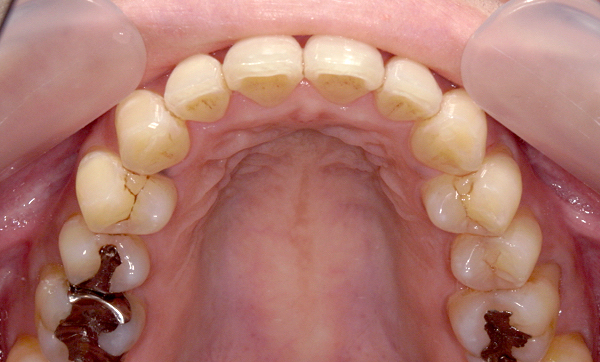

症例_003 前歯「八の字/V字型」症例

治療期間:8ヶ月金額:30万円+税30代女性八の字/V字型上の前歯だけ

| Before | After |